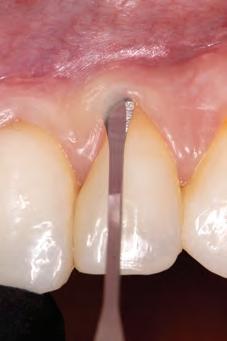

A 31-year-old woman presented with cosmetic concerns regarding her smile and requested a conservative enhancement. After clinical and radiographic analysis, digital 35mm photographs were taken and reviewed by the restorative clinician, technician, and surgeon (Fig 1). A digital impression was taken of the maxillary and mandibular arches using an intraoral scanner (Trios 3, 3Shape; Fig 2), and a smile design was developed with NemoSmile Design 3D software (Nemotec; Fig 3a). This allows for a facially driven smile frame to be created using reference lines of facial and smile proportions and natural teeth shapes and textures from the digital library (Fig 3b).

After developing the simulated mock-up, a 3D-printed resin model was created using CAD software (Fig 4a), and a clear PVS matrix (Exaclear, GC America) was fabricated to replicate the printed diagnostic wax-up using a nonperforated tray (Fig

Fig 1 Preoperative clinical views of a 31-year-old woman presenting with diastemas and limited tooth visibility. (top) Portrait. (center row) Intraoral views. (bottom row) Smile.

4b). This matrix was used to create an intraoral motivational mock-up with bis-acryl composite (Luxatemp Ultra, DMG). This additive mock-up provides the interdisciplinary team with an intraoral translation for evaluation (Fig 5). Upon evaluation of the digital smile frame and the clinical translation, it was determined that multiple esthetic and restorative requirements were necessary for an optimal biologic framework, and the interdisciplinary team determined the best sequence for these procedures. The patient was presented with the interdisciplinary treatment possibilities that included restoring the maxillary anterior teeth and premolars with a minimally

invasive preparationless procedure or with less conservative veneer preparations. The restorative materials discussed included injectable resin composites and ceramic (ie, feldspathic, pressable, machinable). For an optimal biologic framework and health, it was determined that connective tissue grafting would be necessary for treatment of the recessiontype defects on the maxillary left central and lateral incisors, canine, and premolars. The patient opted for the conservative preparationless composite veneers using the injectable resin technique followed by a connective tissue surgical procedure using the tunneling technique.